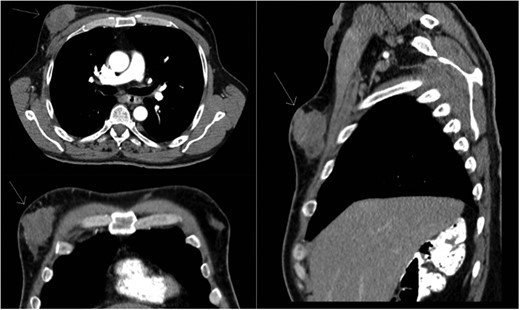

Staging positron emission tomography computed tomography (PET CT) was performed demonstrating activity in the right breast as well as mediastinal and hilar lymphadenopathy (Fig. 2). The patient underwent neoadjuvant chemotherapy and a repeat PET CT showed decreased activity in the right breast and no further lymphadenopathy (Fig. 3). A right modified radical mastectomy was performed. Pathologic examination revealed invasive ductal carcinoma, histologic grade III with closest margin at 1mm away. There was 0 out of 18 positive axillary lymph nodes. Pathologic staging was set at pT2N0M0, Stage IIA. Given the slim posterior margin, he received post mastectomy radiation therapy. Currently, the patient is receiving tamoxifen 20 mg once a day.

Post chemotherapy PET/CT scan. The breast mass decreased in size, with no mediastinal or hilar lymphadenopathy.